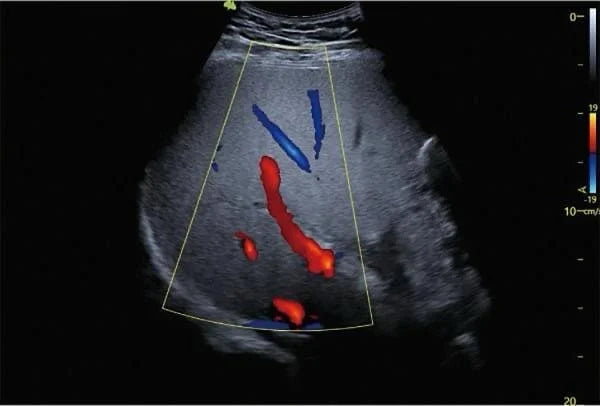

A ultrassonografia Doppler tornou-se uma ferramenta indispensável no diagnóstico de doenças vasculares. A imagem mostra uma representação clara do fluxo sanguíneo em um órgão abdominal, onde as áreas vermelhas e azuis indicam a direção e a velocidade do fluxo, permitindo uma avaliação detalhada da condição dos vasos sanguíneos e do fluxo sanguíneo.

- Doppler colorido: Representa o fluxo sanguíneo com cores (vermelho e azul) para visualizar a direção do fluxo.